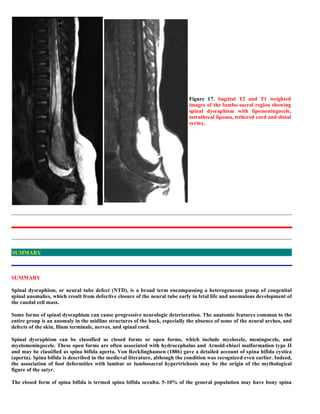

This document discusses a case of occult spinal dysraphism with diastematomyelia and a low tethered spinal cord in an 11-year-old male patient. Radiological findings from X-ray, CT myelography, and MRI show splitting of the spinal cord separated by a bony spur, as well as a dilated subarachnoid space. Occult spinal dysraphism is described as a heterogeneous group of disorders involving anomalies of the spinal cord and meninges covered by an intact skin. Causes may include defects in primary or secondary neurulation leading to conditions like lipomas, tight filum syndrome, and dorsal dermal sinuses. Clinical presentation can include orthopedic deformities and neurological symptoms